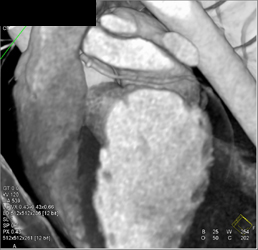

CASE NUMBER 625

Normal Coronary Arteries